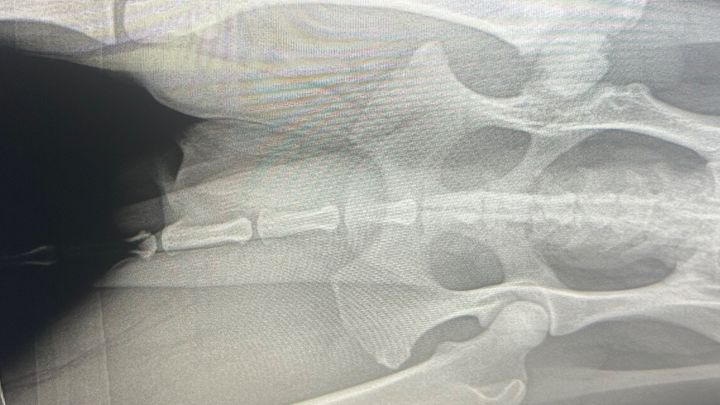

Chili is a barely 2 year old outgoing cattle dog that has been living most of his life in pain. When he was just a little 9 week old baby, an xtra large bully breed attacked him and left his hind leg permanently injured. We took him to 3 different vets who told us his leg was not broken or dislocated, just might be left with a little nerve damage. That was not the case, his leg was damaged much more than we had expected. Overtime, his limp never went away and there are days that he refuses to put pressure on it. We are here to try and raise funds in order to get chili his FHO surgery. I attached a photo of his xray in order to stress the issue as well as a few videos to example his discomfort. Your help and support is so much appreciated❤️we will share more photos after we get this boy healed up. Thank you so much.